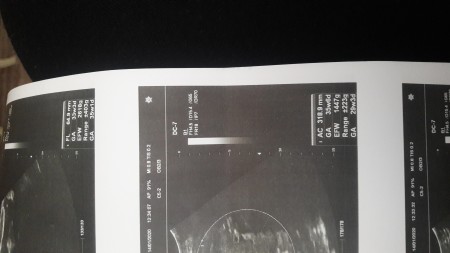

Anne Karninda Bebegin Boyu Ve Kilosu Hafta Hafta Gebelik Hamilelik Takibi Bebek Gelisimi